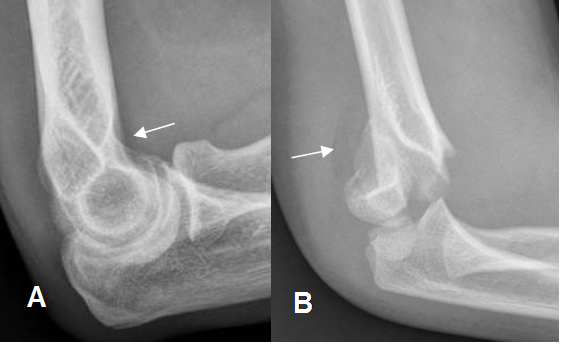

Fig 27. Cojinetes grasos en Rx.

A: Cojinete anterior, en paciente normal.

B: Signos de hemartrosis por fractura supracondilea. Produce desplazamiento del cojinete posterior, hallazgo siempre patológico.